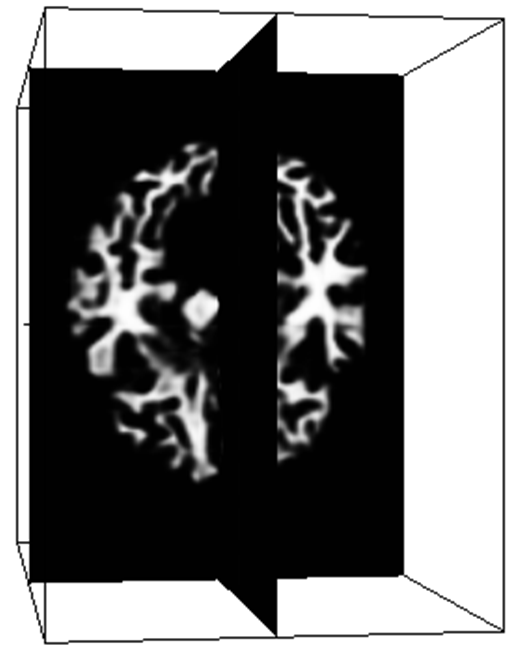

In the up-sampling path, the 3D-Upsampling operators are used to recover the input resolution. In particular, the shallower layers contains the local feature, while the deeper layer contains the global feature [10]. To make a better prediction, we perform up-sampling after each dense block and combine these up-sampling feature maps. The concatenation from the different level of up-sampling feature maps allows capturing multiple contextual information. A classifier consisting of a Conv(1Γ—1Γ—11111\times 1\times 1) is used to classify the concatenation feature maps into target classes (i.e four classes for the brain). Finally, the brain probability maps can be obtained using softmax classification.

To evaluate the performance of the proposed method, we perform cross-validation on iSeg dataset. Fig. 2 shows the validation results of the proposed method for the ninth subject on different slices. This demonstrates the robustness of the proposed network architecture for accurate segmentation.

Figure 2: Segmentation result on different slice (a) T1 image, (b) T2 image, (c) DenseVoxNet, (d) our result, (e) manual segmentation